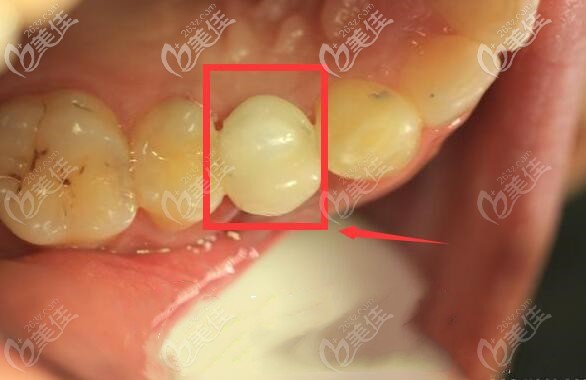

后經(jīng)過六個(gè)月的觀察后發(fā)現(xiàn)修復(fù)效果良好,從圖片可以看出哪個(gè)是種植牙嗎?

種植牙修復(fù)后,種植體與牙槽骨緊密結(jié)合,種植牙與真牙外觀極其相似,上下牙咬合正常,種植體周邊無骨吸收情況??梢哉f手術(shù)是很成功的。